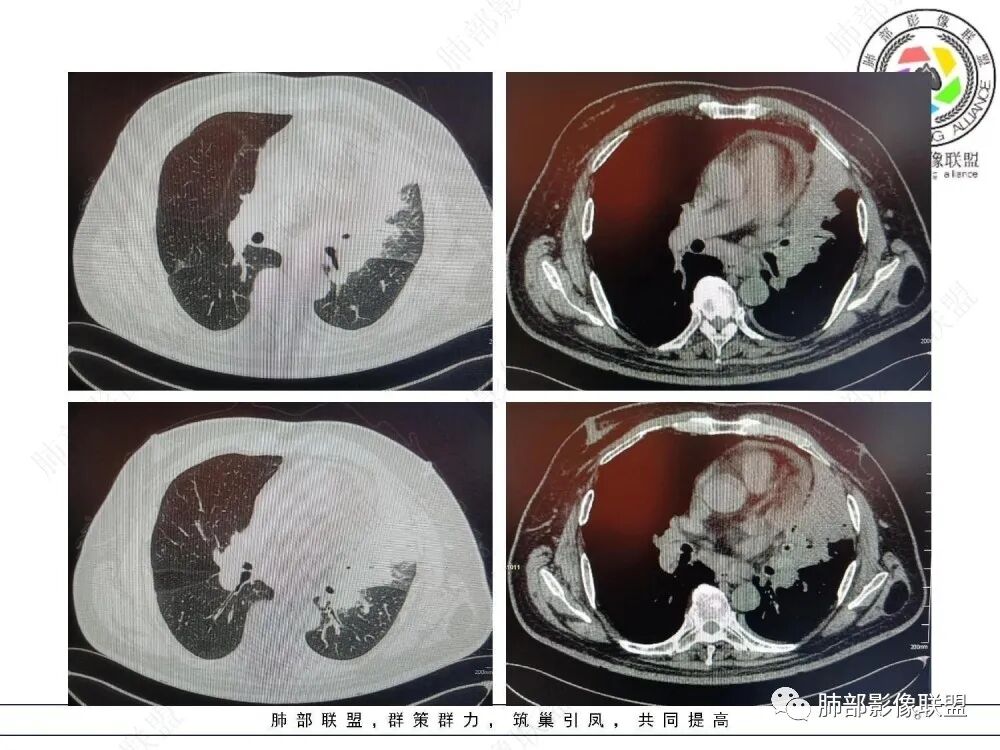

三、影像表现:左肺上叶多发片状高密度影,散在,边缘模糊,支气管壁稍增厚,中轴间质、小叶间隔增厚、有结节感,左肺上叶前段病灶可见胸膜增厚,部分小支气管不能分辨;右肺上叶后段混合磨玻璃结节,边界清,邻近胸膜凹陷;纵膈淋巴结肿大;心包增厚;左侧少量胸水。此外,扫及右侧胸腔内甲状腺肿;左侧肩胛骨旁肌群内脂肪瘤。

四、综合分析:老年男性,以咳嗽咳痰为主要临床表现,无发热,白细胞正常,影像表现为左肺上叶片影,前段结节影、胸膜增厚、部分小支气管不能分辨。左肺上叶中轴间质增厚、小叶间隔增厚、结节感,肺门纵隔见肿大淋巴结,尽管肺部病病灶边缘特征不典型,但高度疑及癌性淋巴管炎这一“次生灾害”却具有相当重要提示意义,而肺癌中最常伴癌淋的就包括腺癌。右肺上叶后段混合磨玻璃结节,边界清楚,张力明显,具有一定特征性,高度指向浸润性腺癌。这对于左肺病灶具有一定程度“助攻”效应。总体而言,本例左肺病灶的诊断关键点在于判断出癌性淋巴管炎。癌性淋巴管炎的结节在外围间质多见,小叶间隔可呈串珠状、结节状增厚,由于出血及水肿,小叶间隔增厚较明显,或呈不规则增厚。有的肺小叶呈多角状阵列。常合并胸水。